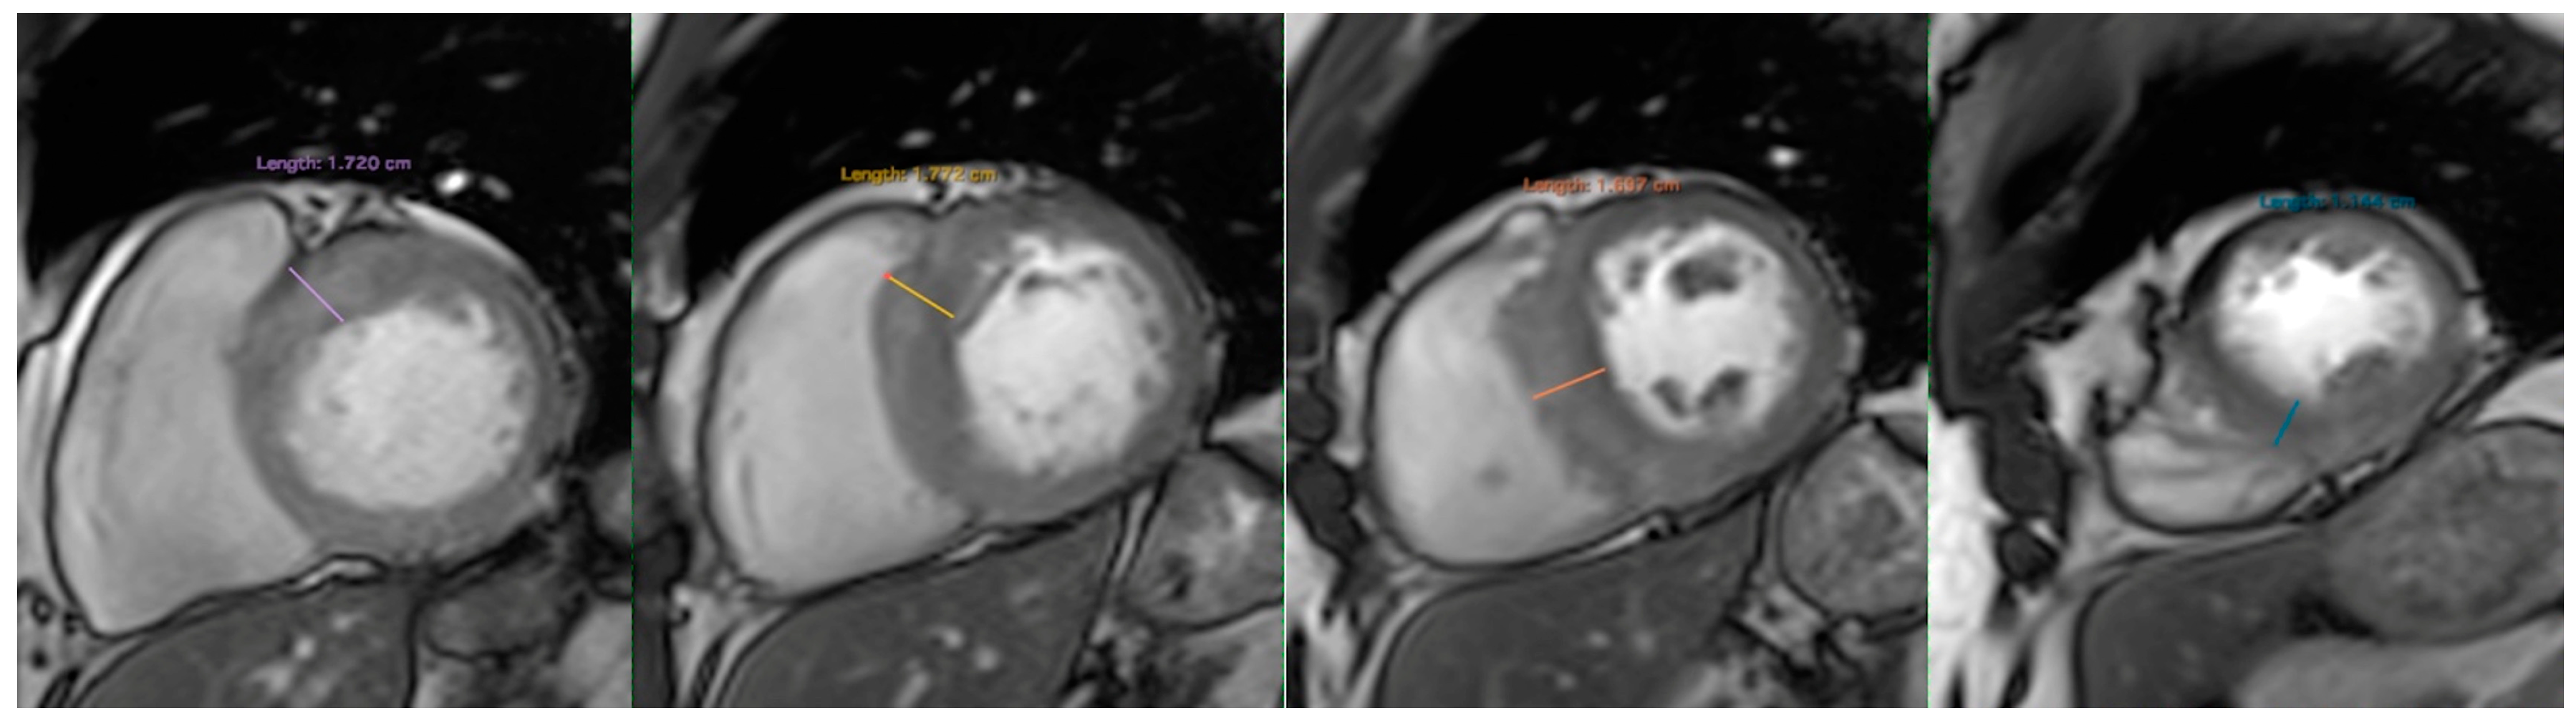

4. Cardiac MRI

6.1. Correlation of LVWT and LVMI with LV Fibrosis